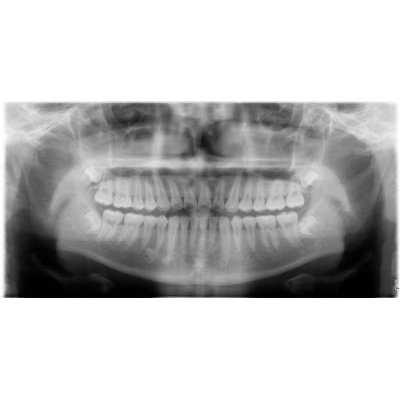

兒童牙科

乳齒:嬰兒出生後第六個月左右第一次長出來的牙會長滿20顆。

預防重於治療。通常在幼兒時期最常見的疾病-齲齒」。愈早作牙齒檢查,便有愈多的機會提早預防牙齒的發生。看牙不一定會痛!在沒有任何的病痛查,對幼兒來說,是一次的愉快經驗。

人工植牙

商品大圖